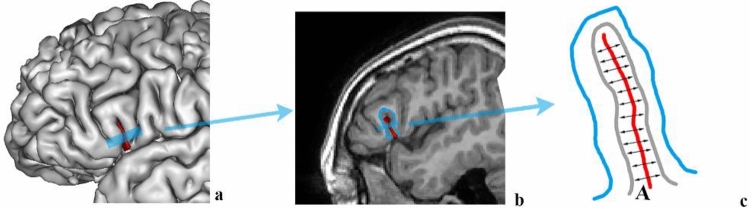

Computation of sulci parameters

Measurements of sulcal length, sulcal width, and sulcal depth required RIC tools for BrainVISA (http://ric.uthscsa.edu/personalpages/petr/). The average sulcal width (AW) for an individual sulcal structure was defined as an average 3D span along the normal projections to the medial sulcal mesh (Kochunov et al. 2005) (Fig. 3). Geometrically, a medial sulcal mesh traverses the sulcal space in the middle of the sulcal “span” dimension, parallel to gyral gray matter borders and spans the entire sulcal “depth” dimension. The sulcal width was calculated as the Euclidean distance between two points on the gyral gray matter mesh on either side of the sulcal surface. The sulcal length consists of the outer length (OL) and inner length (IL). The OL was defined as the length of the lateral edge of the sulcus. The IL was defined as the length of the ridge at the base of the sulcus. The average sulcal depth (AD) was the Euclidean distance between the outer and inner lengths of the sulcal surface (Kochunov et al. 2005, 2008) (Fig. 4).

Fig. 3.

The average sulcal width for an individual sulcal structure is defined as an average 3D distance between opposing points on the GM mesh along the normal projections to the sulcal surface. a snapshot of cortical surface extraction, b the sagittal section. In the schematic drawing on c red line indicates sulcal surface, gray line indicates GM mesh, blue line indicates WM mesh, A indicates sulcal width